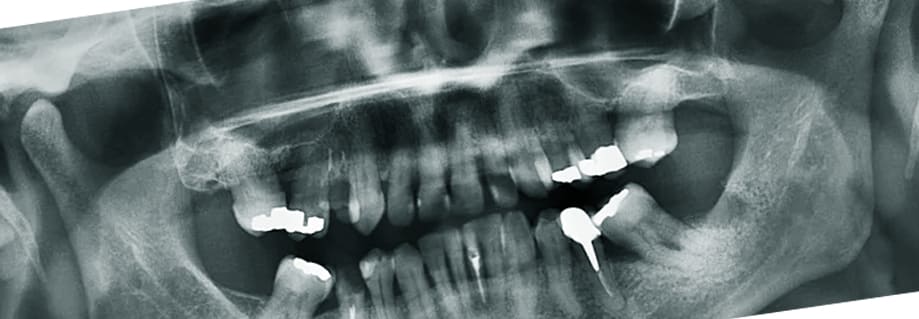

가끔 임플란트 가격이 너무 비싸 틀니로 대체할까 하는 분들이 많은데요. 요즘 임플란트 가격이 굉장히 저렴해 졌을 뿐 아니라 45세 이상에게 다양한 혜택을 제공하고 있고 심지어는 무료 체험하는 이벤트도 많이 있으니 위에 내용을 참고하시면 보다 저렴하게 임플란트를 할 수 있습니다.

임플란트 가격이 해결되면 사실상 틀니를 할지 고민을 하지 않아도 되는데요. 틀니를 하게 되면 임플란트처럼 복잡한 수술은 안해도 되지만 매일 같이 탈착을 해야하는 번거로움이 있고 아주 깨끗하게 위생 관리를 해야 합니다. 이러한 점에 불구하고 임플란트에 비해 저렴하고 신속하기 때문에 아직까지 노인 분들은 틀니를 선호하십니다.

하지만 잇몸 위에 얹어서 사용하는 만큼 밀착력이 뛰어나지 않아 쉽게 분리가 되며 3~4년이라는 짧은 수명을 갖고 있어 교체 비용을 생각하면 임플란트와 크게 차이가 나지 않습니다. 더 나아가 틀니를 탈부착하면서 잇몸뼈가 손상할 수 있기 때문에 비용, 번거로움, 잇몸 건강을 위해서라도 임플란트를 하는 것을 추천합니다.